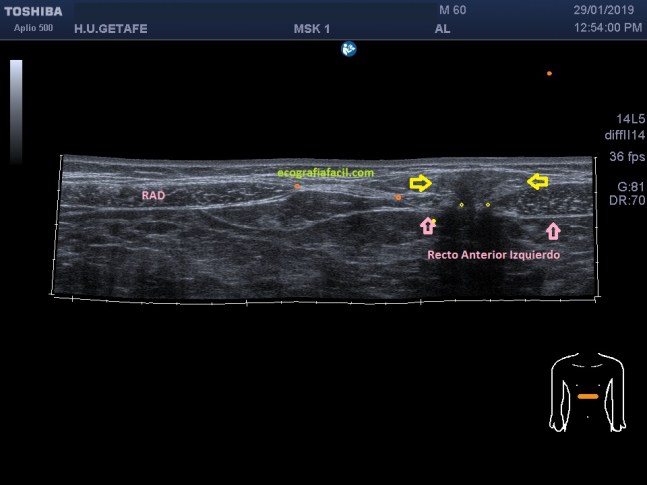

Te lo digo siempre, mucho ojo con las estructuras tendinosas y la anisotropía, sobre todo la de este tendón que pese a estar luxado tiene su ecoarquitectura conservada, pero, en la imagen número 4 puedes ver la imagen del tendón con anisotropía en eje corto y te la pongo para que compares imagen 1 y 2 e imagen 4 y te des cuenta de cómo puede variar una estructura si no realizamos la técnica correctamente. Ojo con esto ya que podemos confundir a la radióloga a la hora de hacer el informe. Combatir la anisotropía es tarea exclusiva del operador

Te marco en la imagen 4 con una línea fina amarilla la corredera bicipital por si te había costado ver la relación con el tendón desplazado y que está indicado con la flecha amarilla, pero anisotrópico.